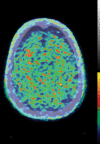

Neurodegenerative diseases are a devastating group of disorders that can be difficult to accurately diagnose. Although these disorders are difficult to manage owing to relatively limited treatment options, an early and correct diagnosis can help with managing symptoms and coping with the later stages of these disease processes. Both anatomic structural imaging and physiologic molecular imaging have evolved to a state in which these neurodegenerative processes can be identified relatively early with high accuracy. To determine the underlying disease, the radiologist should understand the different distributions and pathophysiologic processes involved. High-spatial-resolution MRI allows detection of subtle morphologic changes, as well as potential complications and alternate diagnoses, while molecular imaging allows visualization of altered function or abnormal increased or decreased concentration of disease-specific markers. These methodologies are complementary. Appropriate workup and interpretation of diagnostic studies require an integrated, multimodality, multidisciplinary approach. This article reviews the protocols and findings at MRI and nuclear medicine imaging, including with the use of flurodeoxyglucose, amyloid tracers, and dopaminergic transporter imaging (ioflupane). The pathophysiology of some of the major neurodegenerative processes and their clinical presentations are also reviewed; this information is critical to understand how these imaging modalities work, and it aids in the integration of clinical data to help synthesize a final diagnosis. Radiologists and nuclear medicine physicians aiming to include the evaluation of neurodegenerative diseases in their practice should be aware of and familiar with the multiple imaging modalities available and how using these modalities is essential in the multidisciplinary management of patients with neurodegenerative diseases.©RSNA, 2020.